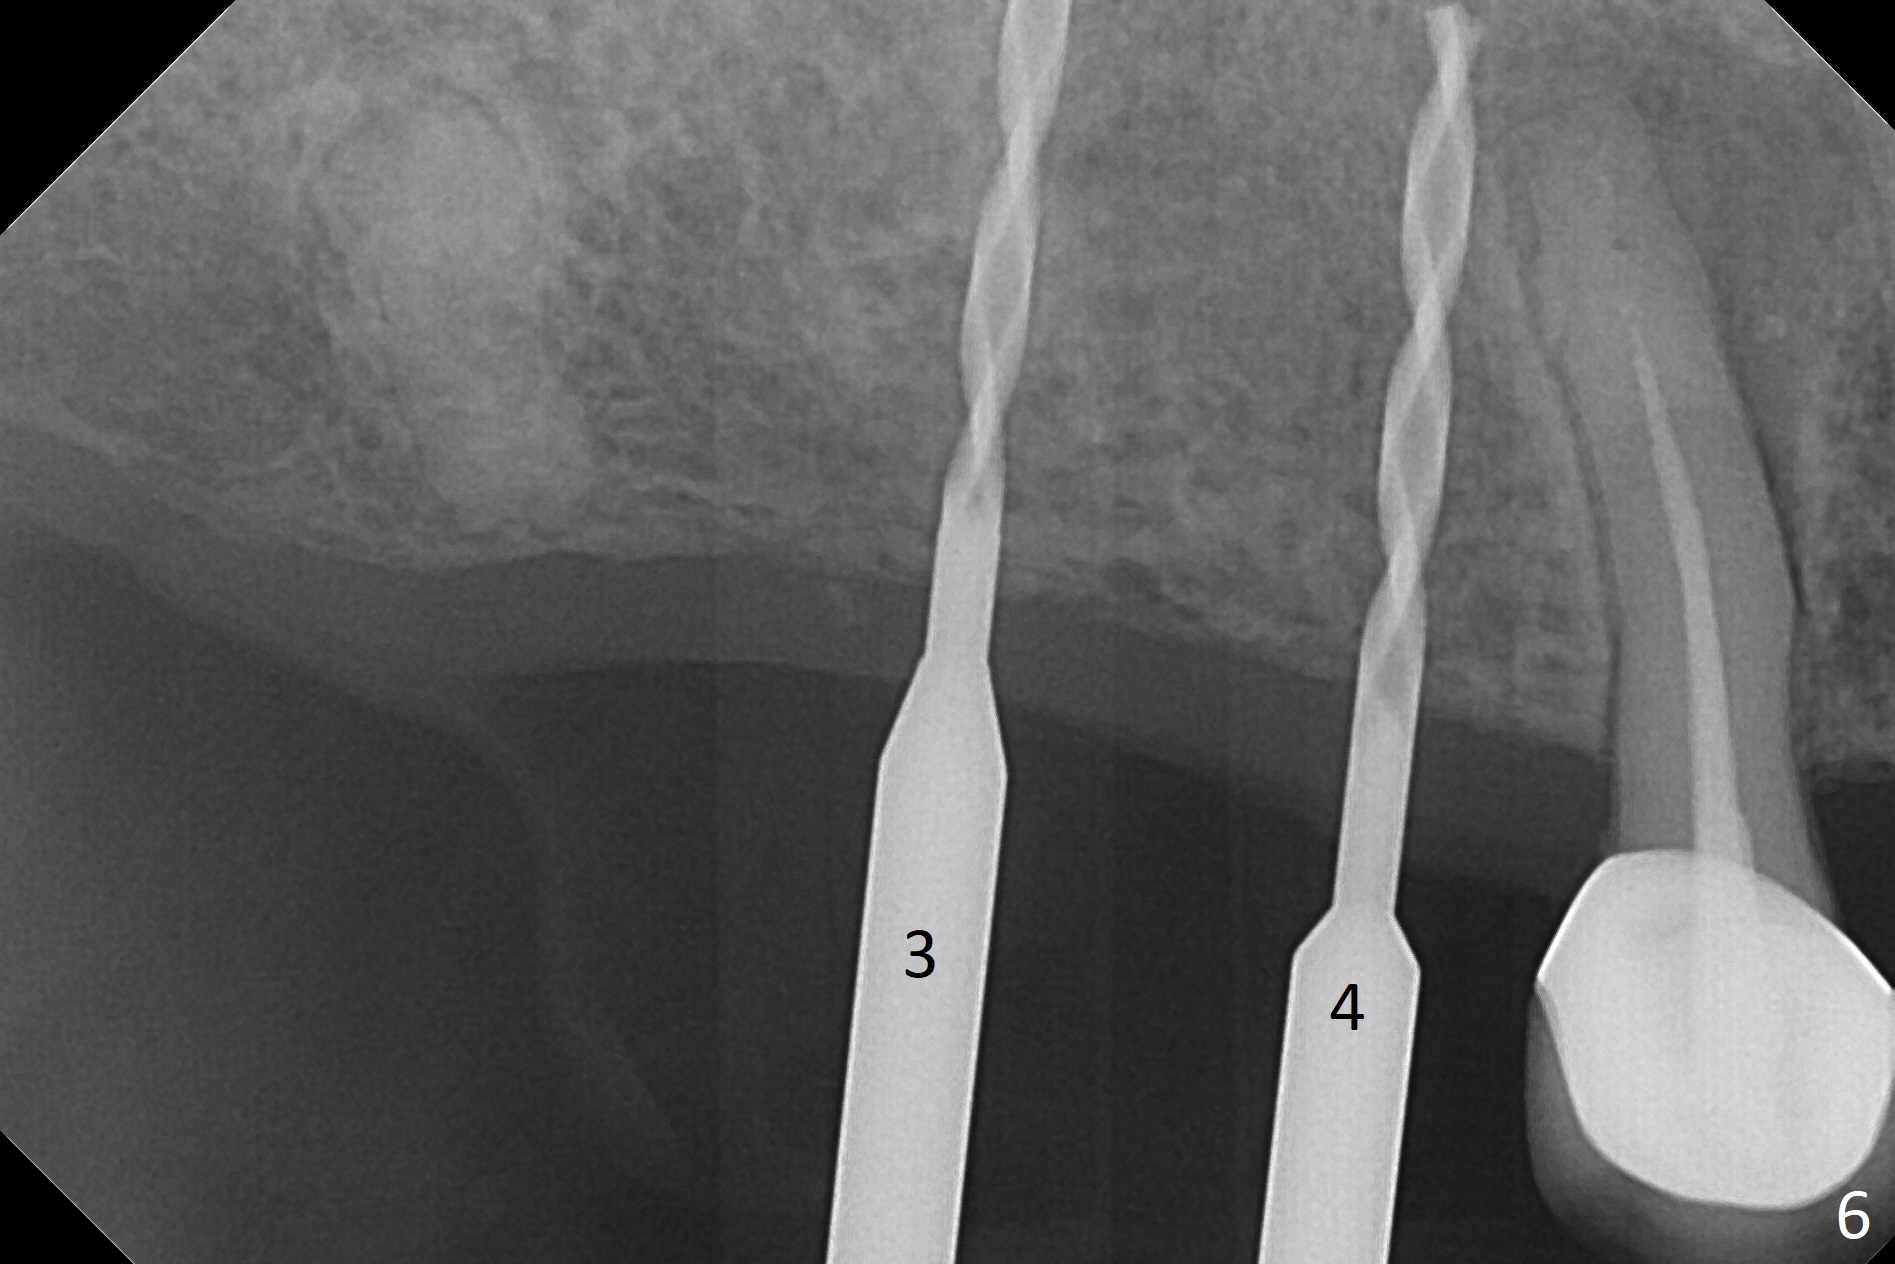

The ridge at #3,4 is wide (Fig.1). A surgical stent is placed (Fig.2) for initial osteotomy (Fig.3). When the stent is removed, the osteotomies need to move palatal (Fig.4 arrows). As two of 1.2 mm drills are in place (Fig.5), mesiodistal trajectories are found off (Fig.6). After the trajectories are corrected (Fig.7), the depth cannot be determined with PA (Fig.8, as compared to Pan (Fig.9)). Following 4.3 and 3.2 mm final drills at #3 and 4, 4.5x13 and 3.8x15 mm implants are placed with insertion torque of 35 and 50 Ncm, followed by 5.5x4(3) and 4.5x4(2) mm abutments (Fig.10). BWs show incomplete placement of the implant at #4 distal (Fig.11,12). Later the implant is placed ~ .5 mm deeper. Periodontal dressing is applied postop. CT-assisted surgical guide must be more efficient for this case with wide ridge. There is no bone loss around the implants 3 moths postop